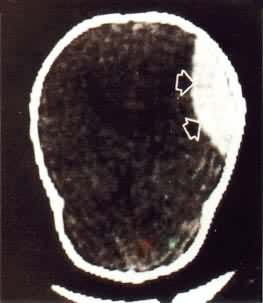

ÄÔ¶¯ÂöÁö£¬ÁöÇ»³öÏÖÁ÷¿ÕÕ÷Ï󣬱íÏÖΪµÍÐźţ¬±ÚѪ˨Ϊ¶ÌT1¡¢³¤T2Ðźţ¬Áö±Ú³ÊµÍÐźŻ·£¨Í¼4£©¡£ÄÔѪ¹Ü»ûÐαíÏÖΪëÏßÍÅ×´»ò·ä·¿×´µÍÐźŲ¡Ô¿É¼ûѪÖס£